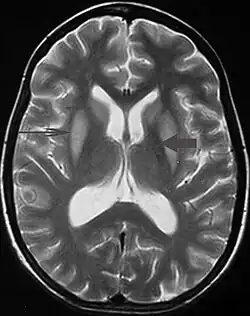

| Axial fat-saturated T2-weighted image showing hyperintensity in the pons with sparing of the peripheral fibers, the patient was an alcoholic admitted with a serum Na of 101 treated with hypertonic saline, he was left with quadriparesis, dysarthria, and altered mental status | |

It can be diagnosed clinically in the appropriate context, but may be difficult to confirm radiologically using conventional imaging techniques. Changes are more prominent on MRI than on CT, but often take days or weeks after acute symptom onset to develop. Imaging by MRI typically demonstrates areas of hyperintensity on T2-weighted images.[30]